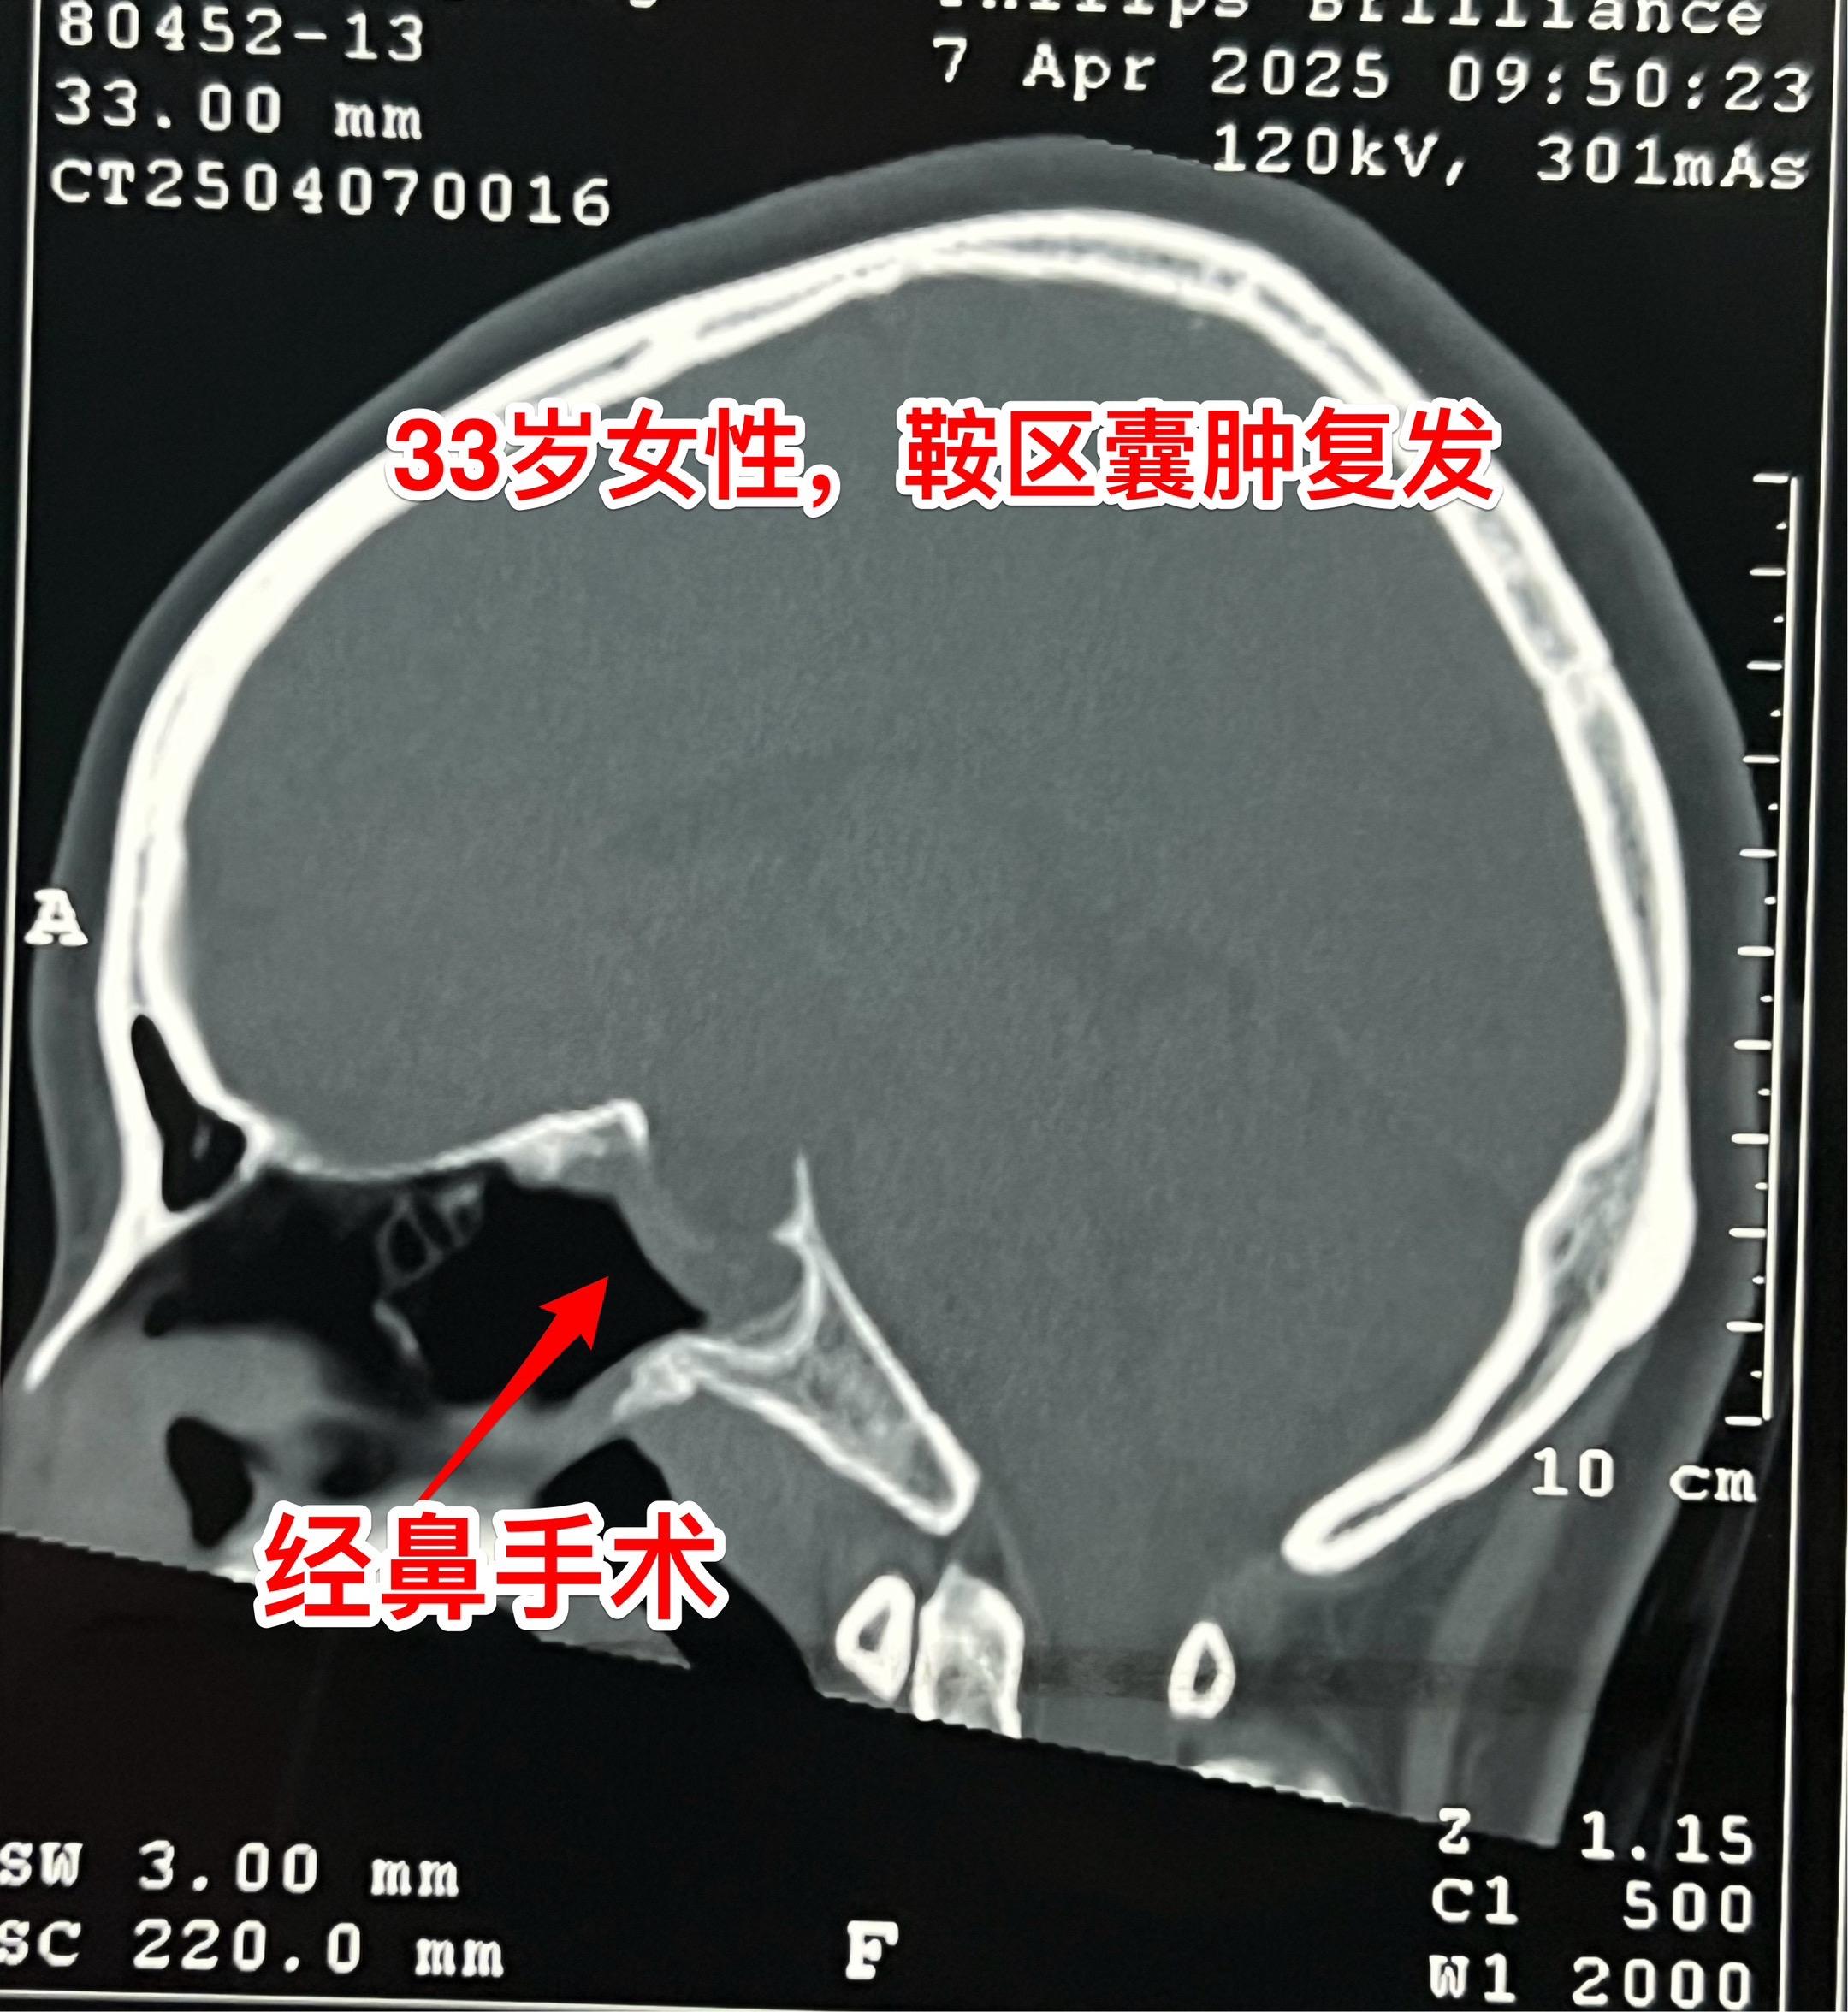

33岁女性鞍区囊肿手术后复发再次手术。这个湖北女性第一次手术是在2025年1月作的经鼻手术,手术后病理报告只看见一些无细胞的结构,没有得出明确的诊断结论(有些遗憾哦)! 手术后两个月患者感觉视野受损,复磁共振显示囊肿和手术之前几乎一样大。 也许是有了心理阴影,这次患者决定找我作开颅手术。开颅手术可以取得确切的病灶标本,最终会得到明确的病理诊断,这是其一大优点! 4月12日作了手术,手术中看见囊肿内涵粘稠液体,可以拉丝,符合拉克氏囊肿。手术中证实:CT上看见的